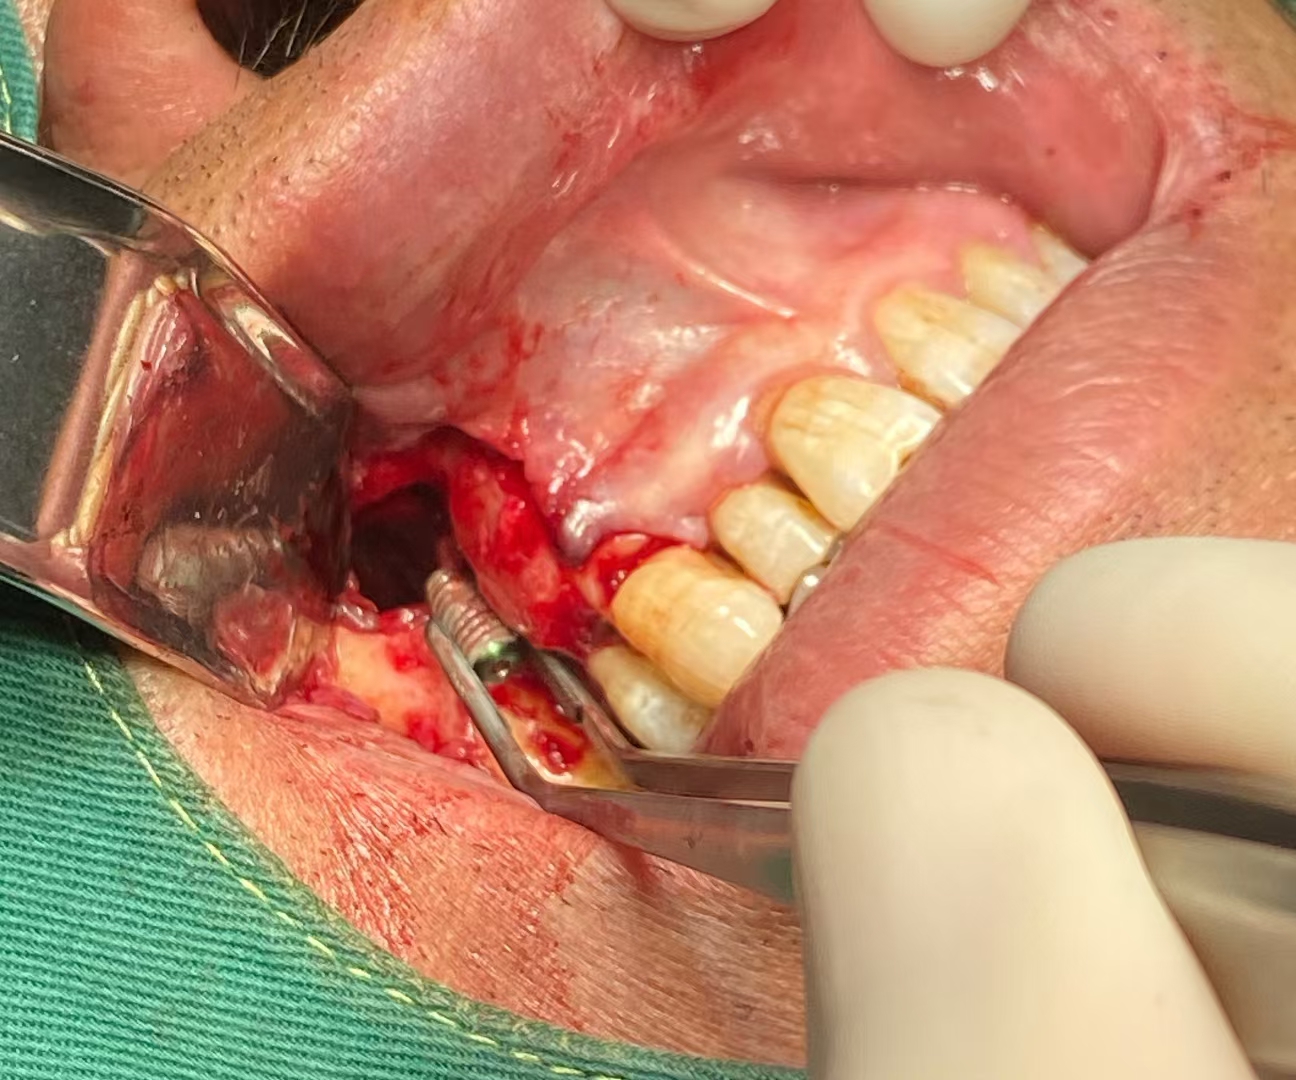

植体掉入上颌窦取出